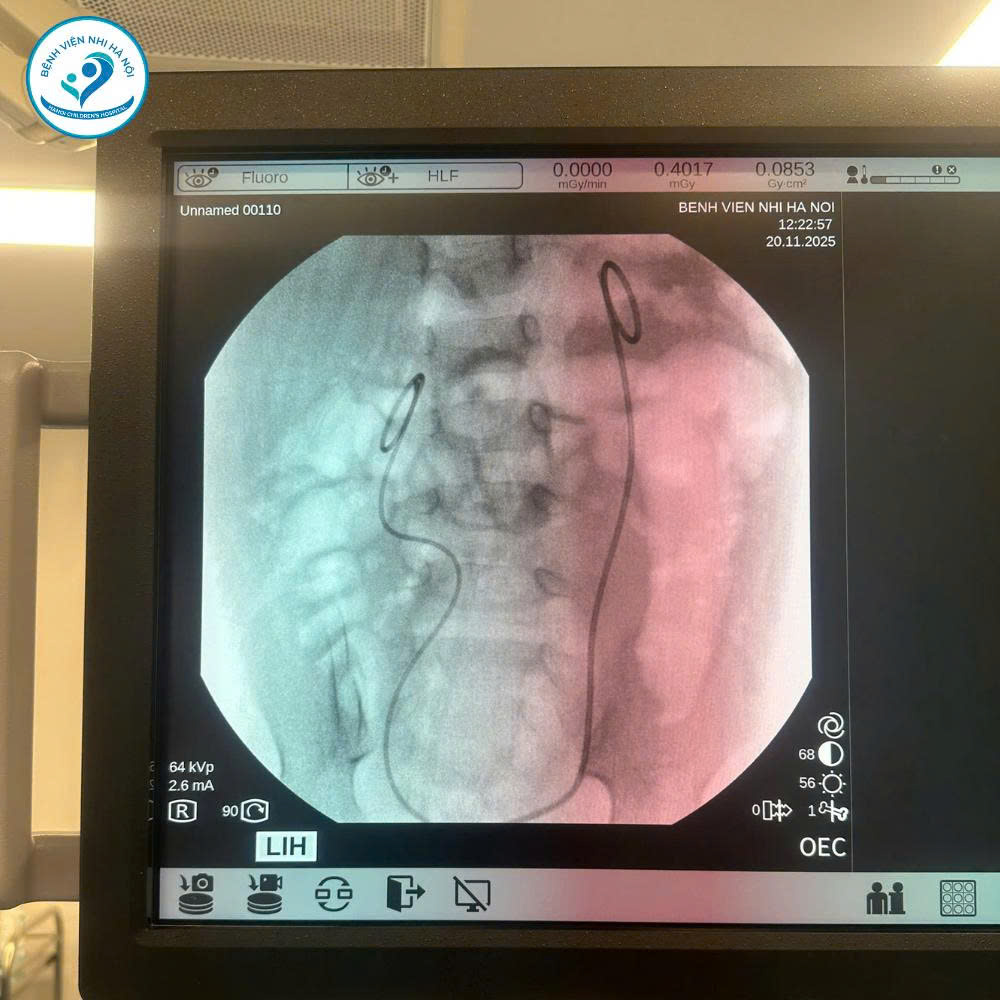

- Tạo hình khúc nối bể thận – niệu quản trái bằng nội soi một lỗ qua rốn

- Đặt JJ bể thận – niệu quản phải ngược dòng